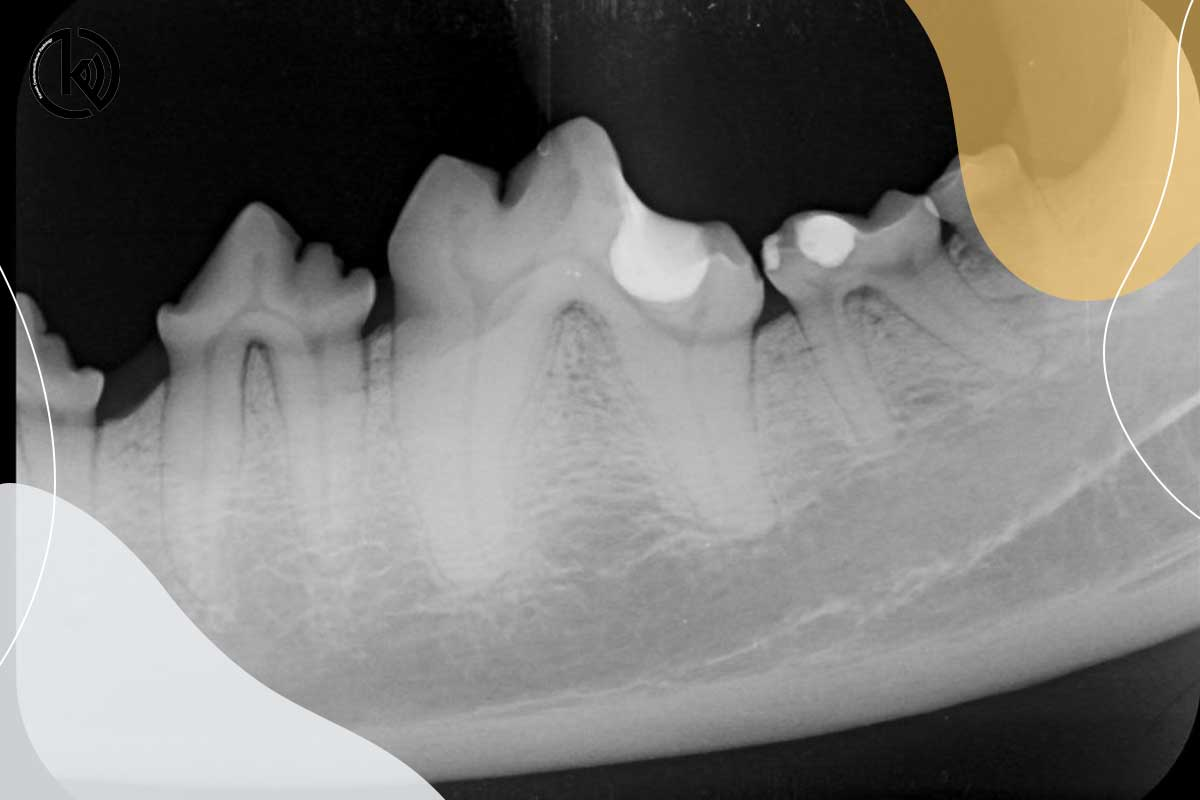

رادیوگرافی کودکان

اهمیت دندانهای شیری امروزه امری ثابت شده است لذا معاینه و چکاپ دندانها یکی از ارکان مهم سلامت دهان میباشد. رادیوگرا...